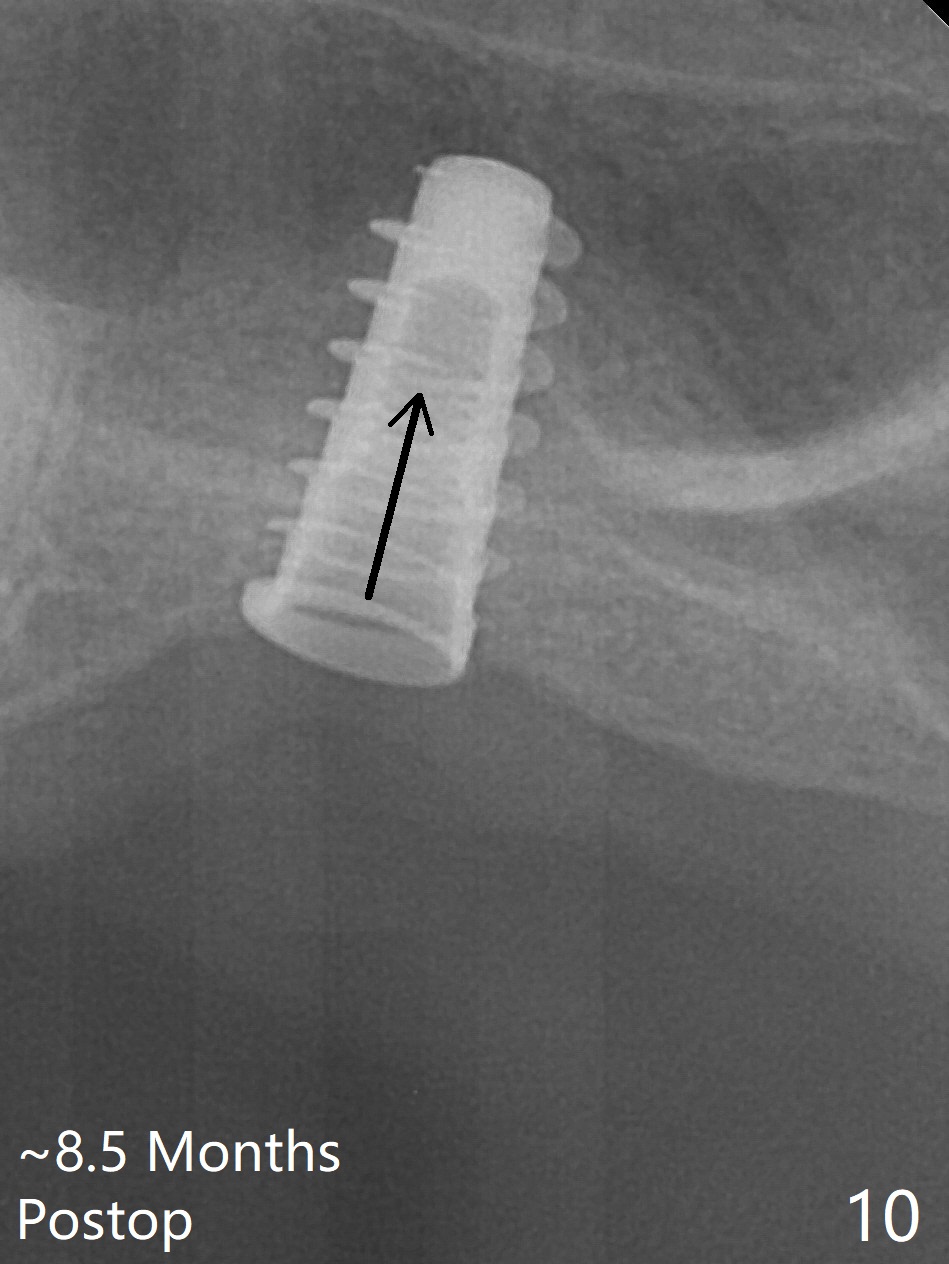

Magic Sinus Lifter is used to elevate the sinus floor for ~ 5 mm, followed by insertion of allograft/Osteogen and 4.0x11 mm dummy implant partially (Fig.1). With approximately 10% more of graft being placed, a 4.5x9 mm IBS implant is placed with insertion torque of 15 Ncm (Fig.2). The implant has a tenting effect. The bone graft appears to move distal 1 month 20 days postop (Fig.5 arrow), while the implant seems to be extruded with implant exposure. The patient feels pain when the healing screw is being removed or tightened. The distal migration of the bone graft may lay foundation for future implant placement at #15. Can the implant at #14 be retorqued to be seated deeper 3-4 months later? Bone density around the implant remains the same (Fig.6), while the wound reduces nearly 3.5 months postop (Fig.7). There are two layers of the bone, one (1) being denser than the other (2) 8 months postop (Fig.8). After local anesthesia, the healing screw is removed; the implant is found to be stable. A 6x4(2) mm pair abutment cannot be inserted due to blockage of the mesiobuccal gingiva (Fig.9 *). Instead a 6x2 mm healing abutment is placed. Three weeks later (approximately 8.5 months postop), the implant is found to be able to rotate when a 6.5x5.7(1) mm pair abutment is tightened with local anesthesia (there is pain associated with healing screw removal). After removal of the latter, the implant is placed deeper by hand retightening (Fig.10 arrow). Is it a better idea to use a new larger implant instead? The patient (53 years old) is scheduled to return for follow up in 3 months.